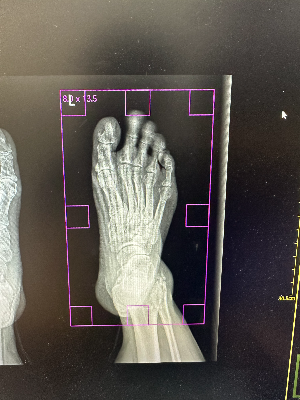

환자의 흔들림에 의해 모션 아티팩트가 발생하여 나온 X-ray 엑스레이 영상 모습